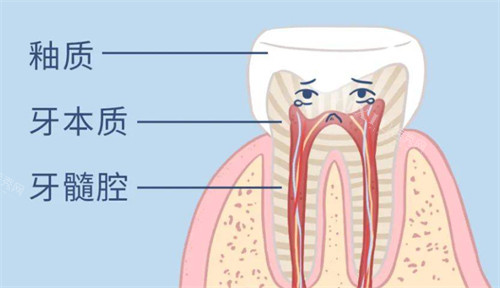

根管治疗:1300 / 根